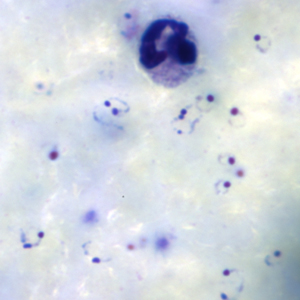

Ring-form trophozoites of P. falciparum in thick and a thin blood smear.

Microscopy (morphologic analysis) continues to be the “gold standard” for malaria diagnosis. Parasites may be visualized on both thick and thin blood smears stained with Giemsa, Wright, or Wright-Giemsa stains. Giemsa is the preferred stain, as it allows for detection of certain morphologic features (e.g. Schüffner’s dots, Maurer’s clefts, etc.) that may not be seen with the other two. Ideally, the thick smears are used to detect the presence of parasites while the thin smears are used for species-level identification. Quantification may be done on both thick and thin smears.